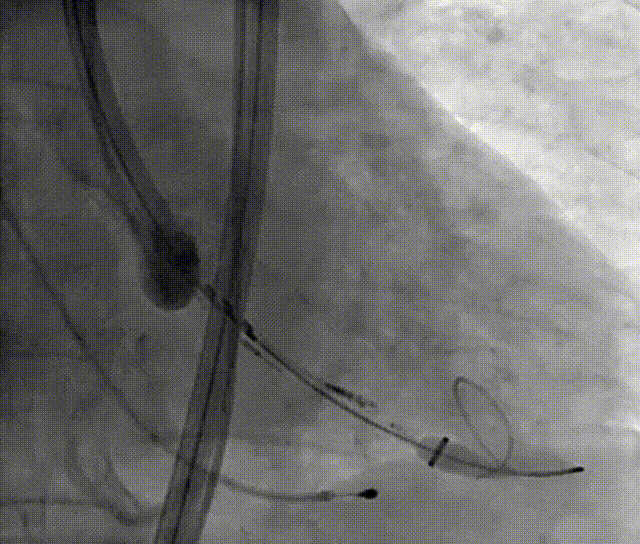

4. 双侧冠脉造影;

5. 右窦中心投照体位行主动脉根部造影;

6. AL2导管配合直头导丝跨瓣,交换加硬钢丝于左心室;

7. 22mm球囊预扩张;

8. 25mm Silara主动脉瓣膜过弓、跨瓣及定位;

9. 25mm Silara主动脉瓣膜左心室初步释放,瓣膜功能良好(不需要左心室快速起搏);

10. Silara 主动脉瓣膜提拉至瓣环水平,精准定位瓣膜,造影剂显示瓣膜功能良好,完成固化;

11. 最终造影瓣膜位置理想,无返流及瓣周漏。